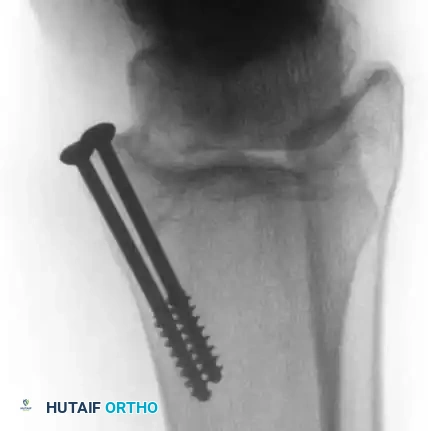

* Approach: Anterolateral lesions can often be accessed via a small arthrotomy. Posteromedial lesions frequently require a medial malleolar osteotomy for perpendicular access.

Fig. 16: Preparation for an OATS procedure. A medial malleolar osteotomy is performed to gain perpendicular access to a large posteromedial lesion.